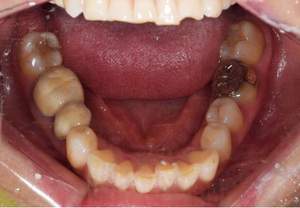

症例写真(治療前)

治療前:

八重歯が目立ちます。また銀歯もおおく、見た目が気になります。虫歯も散見できます。

治療中

矯正装置をつけています。だんだん八重歯が動いてきているのがわかります。今回のケースでは、抜歯を行わずに矯正ができました。